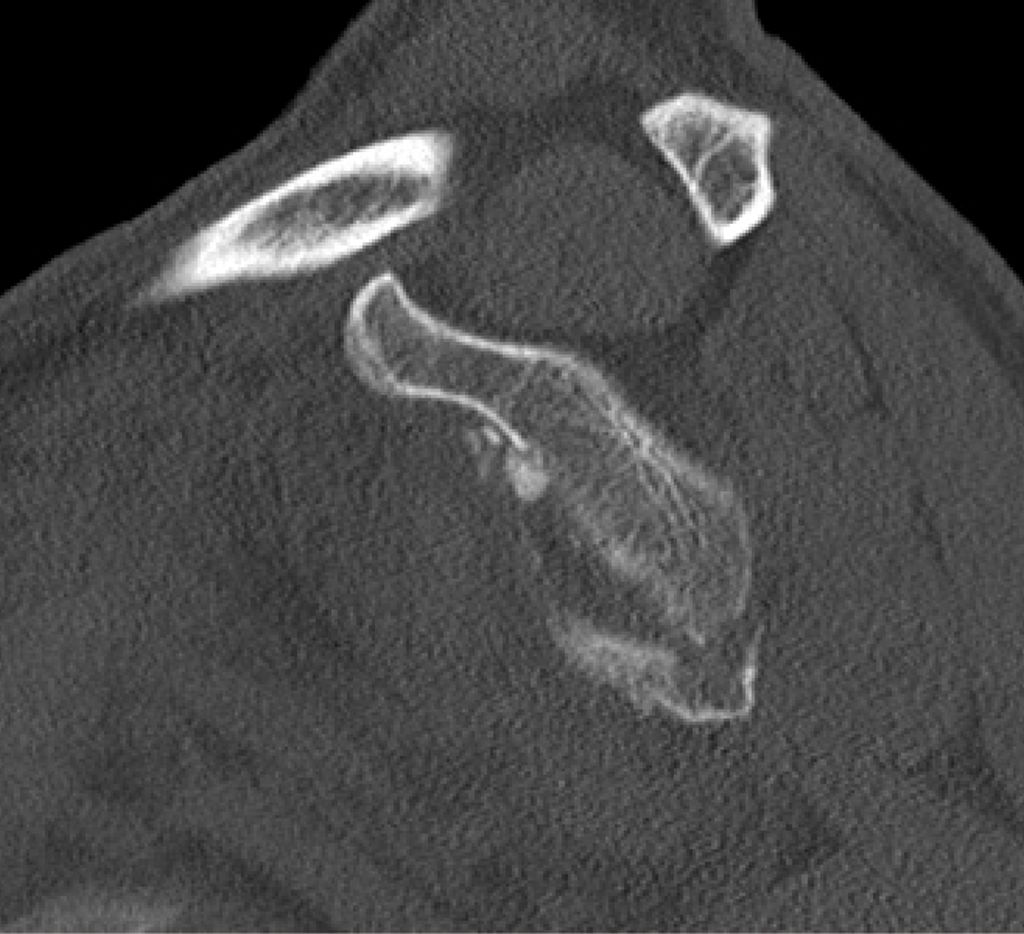

Der operative Eingriff wird in Beach-Chair- oder Seitenlagerung durchgeführt, wobei der betroffene Arm in einem Armhalter frei beweglich gelagert wird. Nach Etablierung der Standardportale – bestehend aus einem posterioren Portal zur Optik sowie anterior-inferioren und anterior-superioren Arbeitsportalen – erfolgt die arthroskopische Inspektion des Glenohumeralgelenks. Als Nächstes wird ein zusätzliches transsubskapuläres Portal (5-Uhr-Portal) angelegt (Abb.3). Die Frakturpräparation umfasst die Entfernung von Hämatom- und Interpositionsgewebe, die Mobilisation des Fragments sowie das Anfrischen der Frakturflächen zur Optimierung der knöchernen Heilung. Die Reposition erfolgt unter arthroskopischer Sicht mithilfe geeigneter Repositionsinstrumente, gegebenenfalls unterstützt durch temporäre Fixation mittels Kirschner-Draht (Abb.4).